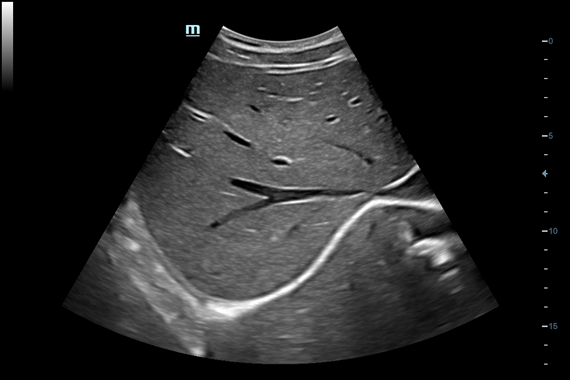

Система ультразвукового исследования Mindray DC-60 EXP X-INSIGHT является новейшей разработкой для проведения комплексных обследований на высшем уровне. Она обеспечивает решение самых сложных задач в таких областях, как кардиология, акушерство и гинекология, сосудистые заболевания, педиатрия и многие другие.

DC-60 EXP X-INSIGHT - это современный стационарный УЗИ-аппарат с функцией сенсорного управления и очищенной гармонической визуализацией, обеспечивающей лучшее контрастное разрешение и технологию 4D-визуализации. Он оснащен 21,5-дюймовым монитором, который может поворачиваться на 180 градусов, что удовлетворяет потребности врачей в качественной ультразвуковой диагностике.

• Поддержка режимов сканирования B/M/Цветовой доплер CDI/Цветной M/Энергетический доплер PD/Направленный энергетический доплер Dir.PD.

Одним из ключевых преимуществ DC-60 EXP X-INSIGHT является технология формирования УЗ-луча. Она дополняет основной луч параллельно эхо-сигналами, что приводит к получению более мощного сигнала и изображений высокого качества с помощью систем iLive, iPage, Smart OB, Smart NT.